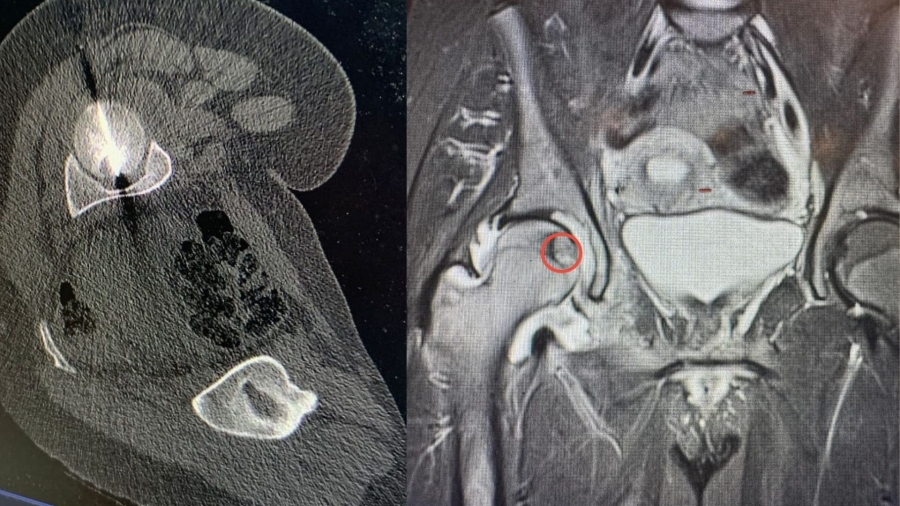

وبين البطوش، أن الفريق الطبي نجح في الوصول إلى مركز الورم بدقة عالية باستخدام تقنية التصوير الطبقي المحوري (CT Scan)، تلا ذلك إجراء الكي بالتقنية الحرارية باستخدام المايكروويف، وهي من أحدث التقنيات العالمية في علاج أورام العظام دون الحاجة إلى التدخل الجراحي المفتوح.